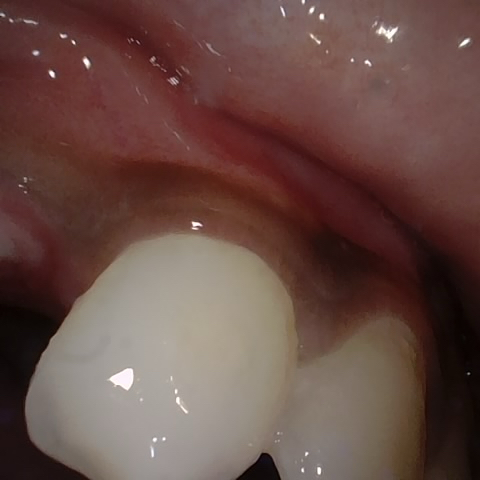

Annotated as "Good"